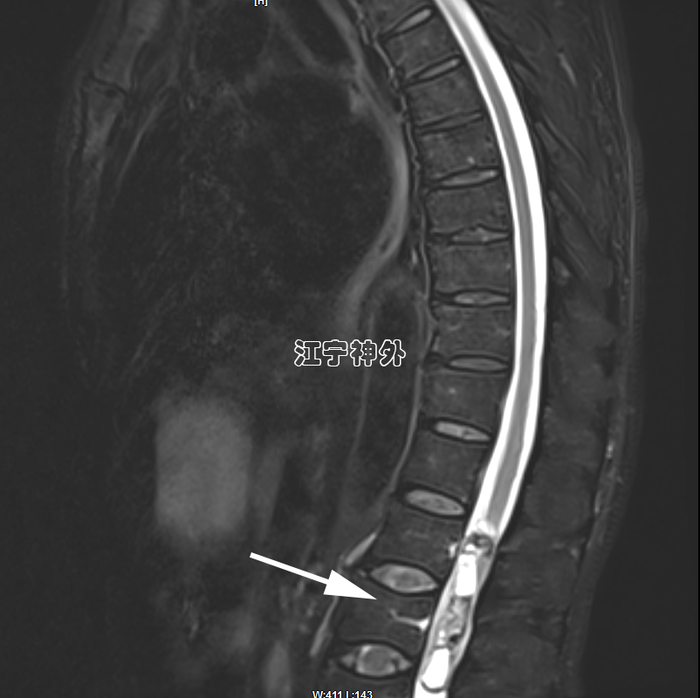

病例2:患者老年男性,因记忆力下降、行走不稳、经常跌倒、有时尿失禁来院,从症状来看,非常符合正常颅压脑积水的表现,而且CT上也确实存在脑室增大,因此就诊神经外科郑学胜主任门诊,并收治入院。然而,术前检查常规做腰穿时,发现脑脊液是草黄色的,压力也很低,提示椎管内存在梗阻性病变。于是,郑主任团队予以全脊柱增强磁共振检查,发现腰1-2水平巨大椎管肿瘤,很显然,上述行走不稳、跌倒、尿失禁等症状是椎管肿瘤引起的。

郑主任阅片发现,从横断面来看,肿瘤几乎占据了椎管全径,正常的脊髓圆锥和神经根已不可辨认,很难说是髓外硬膜下病变还是髓内病变。结合病程很长,脑脊液循环已完全阻断,推测肿瘤与脊髓圆锥、马尾神经根之间,以及肿瘤与硬脊膜之间很可能有明显粘连,所以手术难度较大,手术风险高。